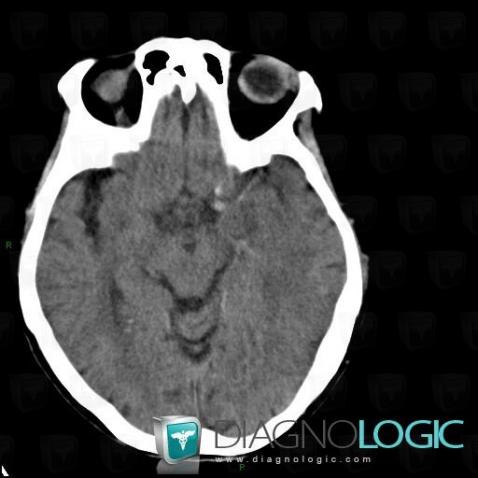

Arterial thrombosis, Cerebral arteries, CT

Here is the specific information in the key image above:

- Diagnosis Arterial thrombosis, Location(s) Cerebral arteries, with gamuts